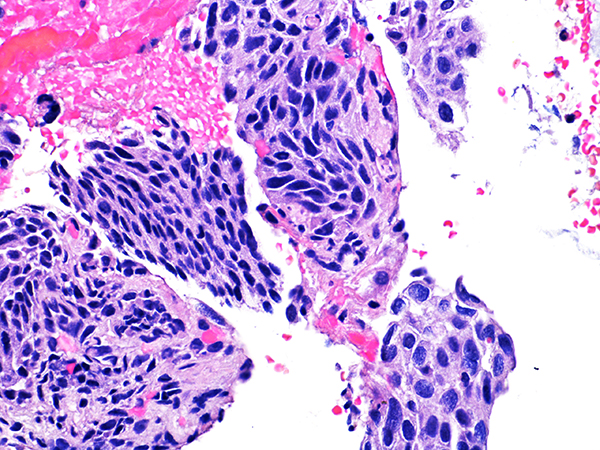

![]() Case 2

Soft Bx CIN 2

40x - High Power